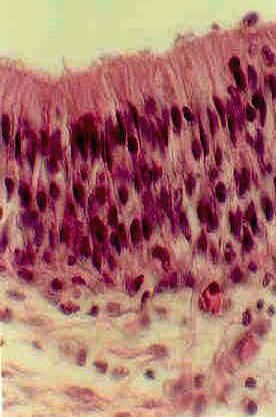

The nuclei nearest the lumen belong to the Sustentacular cells. They are elongated. The middle layer of nuclei are rounder and somewhat paler. These belong to the Olfactory cells. The nuclei of the Basal cells are the third layer, nearest the connective tissue. They may be difficult to identify. Study an electron micrograph of Olfactory cells and learn how they are specialized for olfactory sensation. Also, learn the function of each of these three cell types.

Underneath the epithelium is connective tissue called the Lamina Propria, which is loose connective tissue. You can identify glands which produce the fluid that dissolves substances to be smelled. These are called Bowman's glands. You can also see large nerve fiber bundles of Cranial Nerve I.called the Filia Olfactoria. These will synapse in the olfactory bulb.